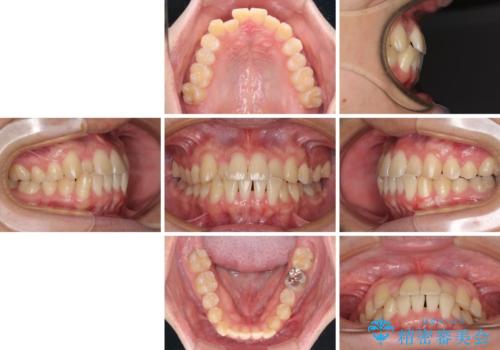

- 前歯のクロスバイトを気にして来院された患者様です。

骨格的には問題がなかったため、インビザラインを用いて咬み合わせを改善していくこととしました。

インビザライン特有の、奥歯の咬み合わせの問題もなく、しっかりと歯列を改善することができました。

舌側転位している上顎側切歯(内側に引っ込んでいる真ん中から2番目の歯)は、インビザラインが最も移動を苦手とする歯であり、これ以上の改善を望まれる場合にはワイヤー矯正、あるいはワイヤー矯正の併用をお勧めいたします。